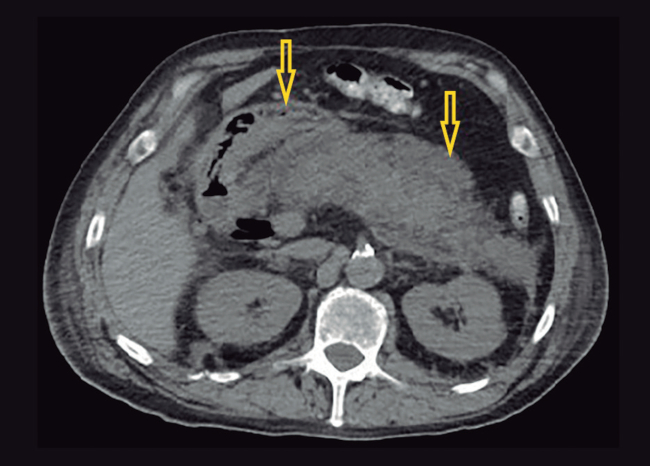

Se realiza papilectomía endoscópica y se presenta como complicación una pancreatitis aguda severa necrotizante. A las cuatro semanas, el paciente evoluciona febril, con tomografía computada que evidencia un marcado aumento difuso del volumen y el tamaño del páncreas, asociado a múltiples colecciones heterogéneas, con pared definida amurallada con componente mixto a predominio líquido, imágenes aéreas en su interior localizadas en la región peripancreática, predominando dos colecciones definidas en cuerpo y cola (69 x 50 mm y 77 x 54 mm), con extensión a espacio perirrenal, raíz del mesenterio y ambas goteras parietocólicas, sin realce tras la administración de contraste, lo que sugiere necrosis (Figura 1). Debido a la naturaleza predominantemente líquida de las colecciones, se colocan inicialmente dos drenajes percutáneos guiados por tomografía hacia colección de cuerpo y cola, con lavajes diarios con solución fisiológica. Se aísla por cultivo Acinetobacter baumanii. El paciente evoluciona tórpidamente, manteniéndose febril de manera persistente y se agrega falla multiorgánica. En control tomográfico se observa una franca disminución de colección de localización cefálica con persistencia en cola de páncreas en el espacio perirrenal y en espacio gastropancreático, sin contacto con la pared gástrica (Figura 2). Por persistencia de walled-off necrosis en cola de páncreas, ausencia de contacto con pared gástrica o duodenal, y sin contar en la institución con endosonografía sumado a mala respuesta clínica, se decide el abordaje endoscópico transcutáneo con colocación de stent metálico esofágico autoexpandible parcialmente cubierto.